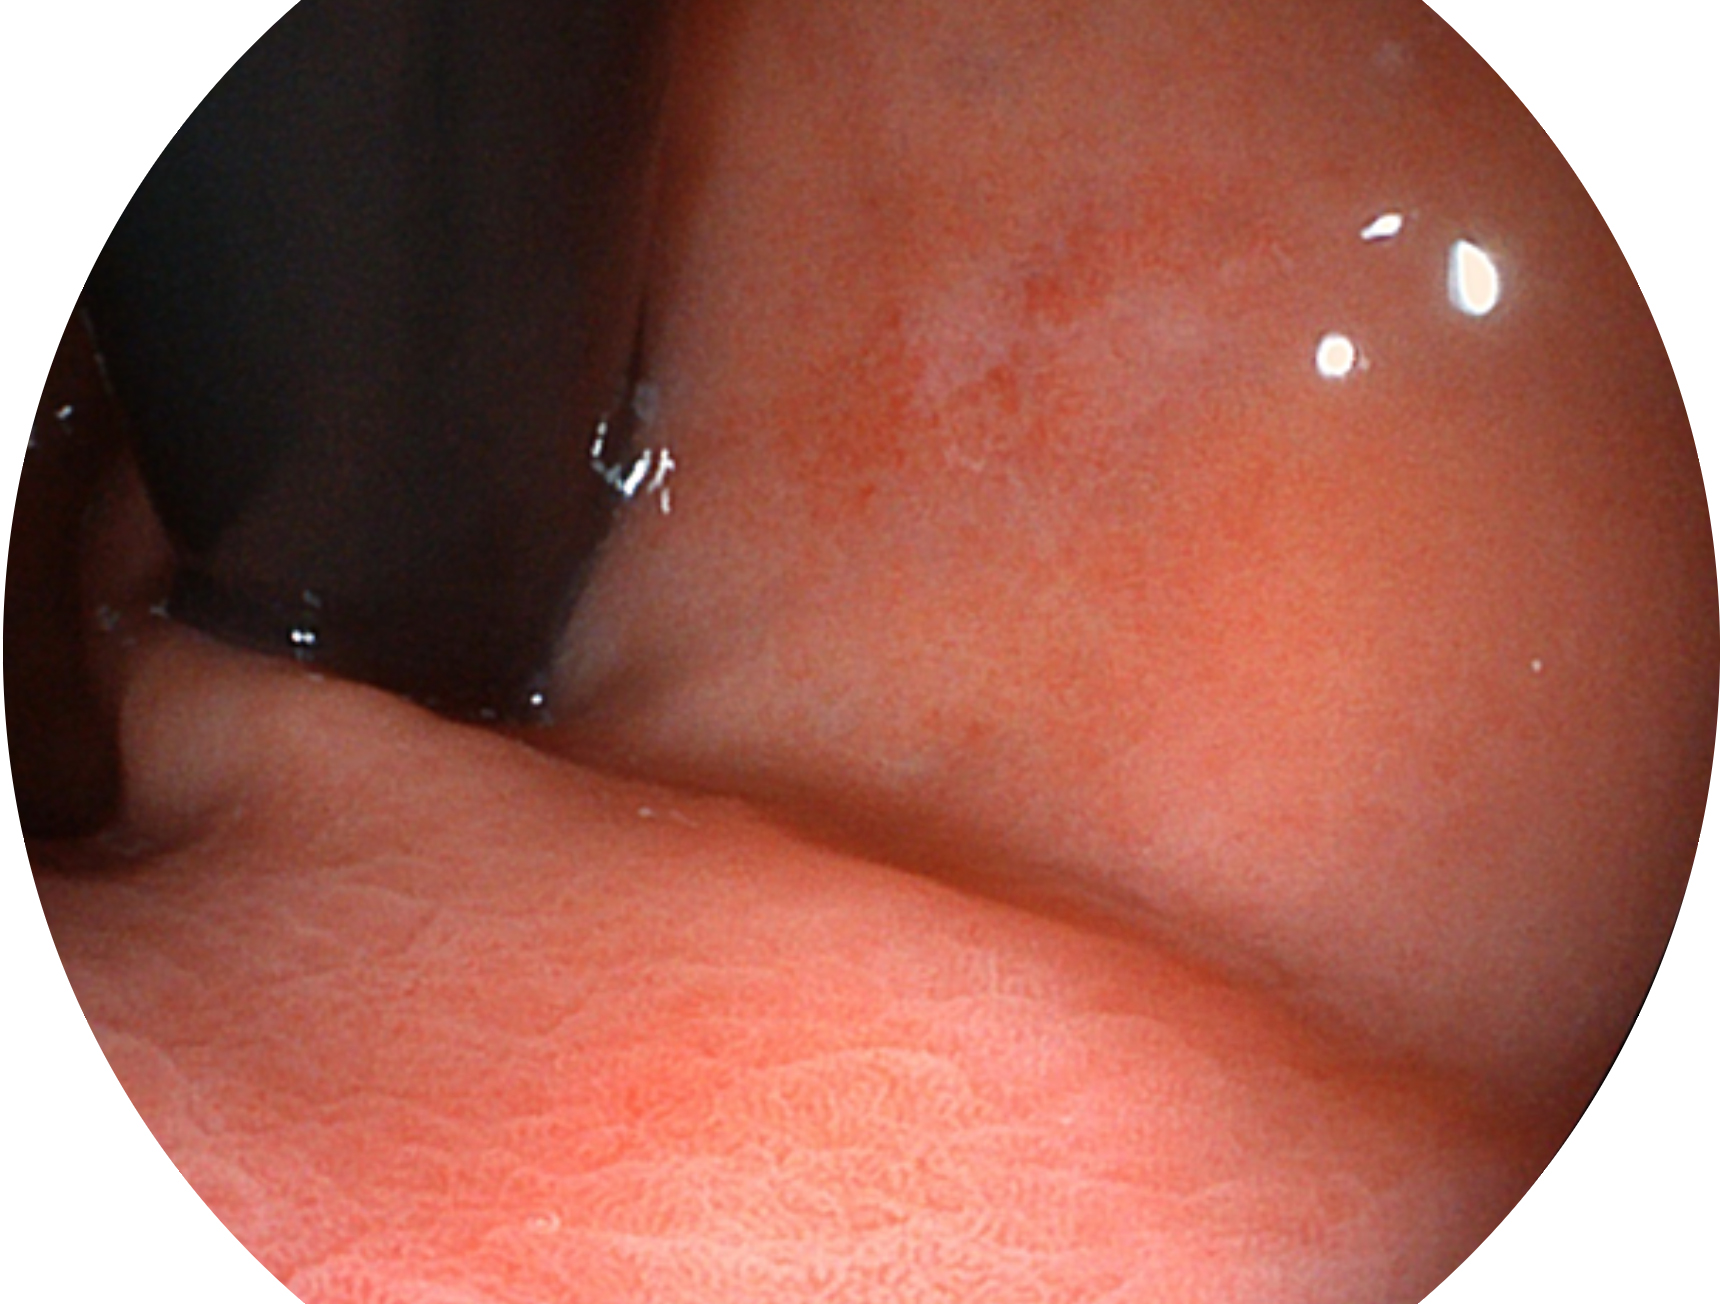

球速体育入口新开发的内镜染色技术,主要是基于多波长LED 光源的开发,VLS-55Q 四波长LED 光源是由四个不同颜色的LED光按照相应照明模式所规定的特定发光比例进行合束后形成,合束后形成的照明光的光谱由红光、绿光、蓝光及蓝紫光这四个不同的波段范围构成。具有更高光谱自由度,通过光谱比例的控制,实现了聚谱成像技术,英文全称为“Spectral Focused Imaging, SFI”,缩写为“SFI”和光电复合染色成像技术,英文全称为“Versatile Intelligent Staining Technology, VIST”,缩写为“VIST”。